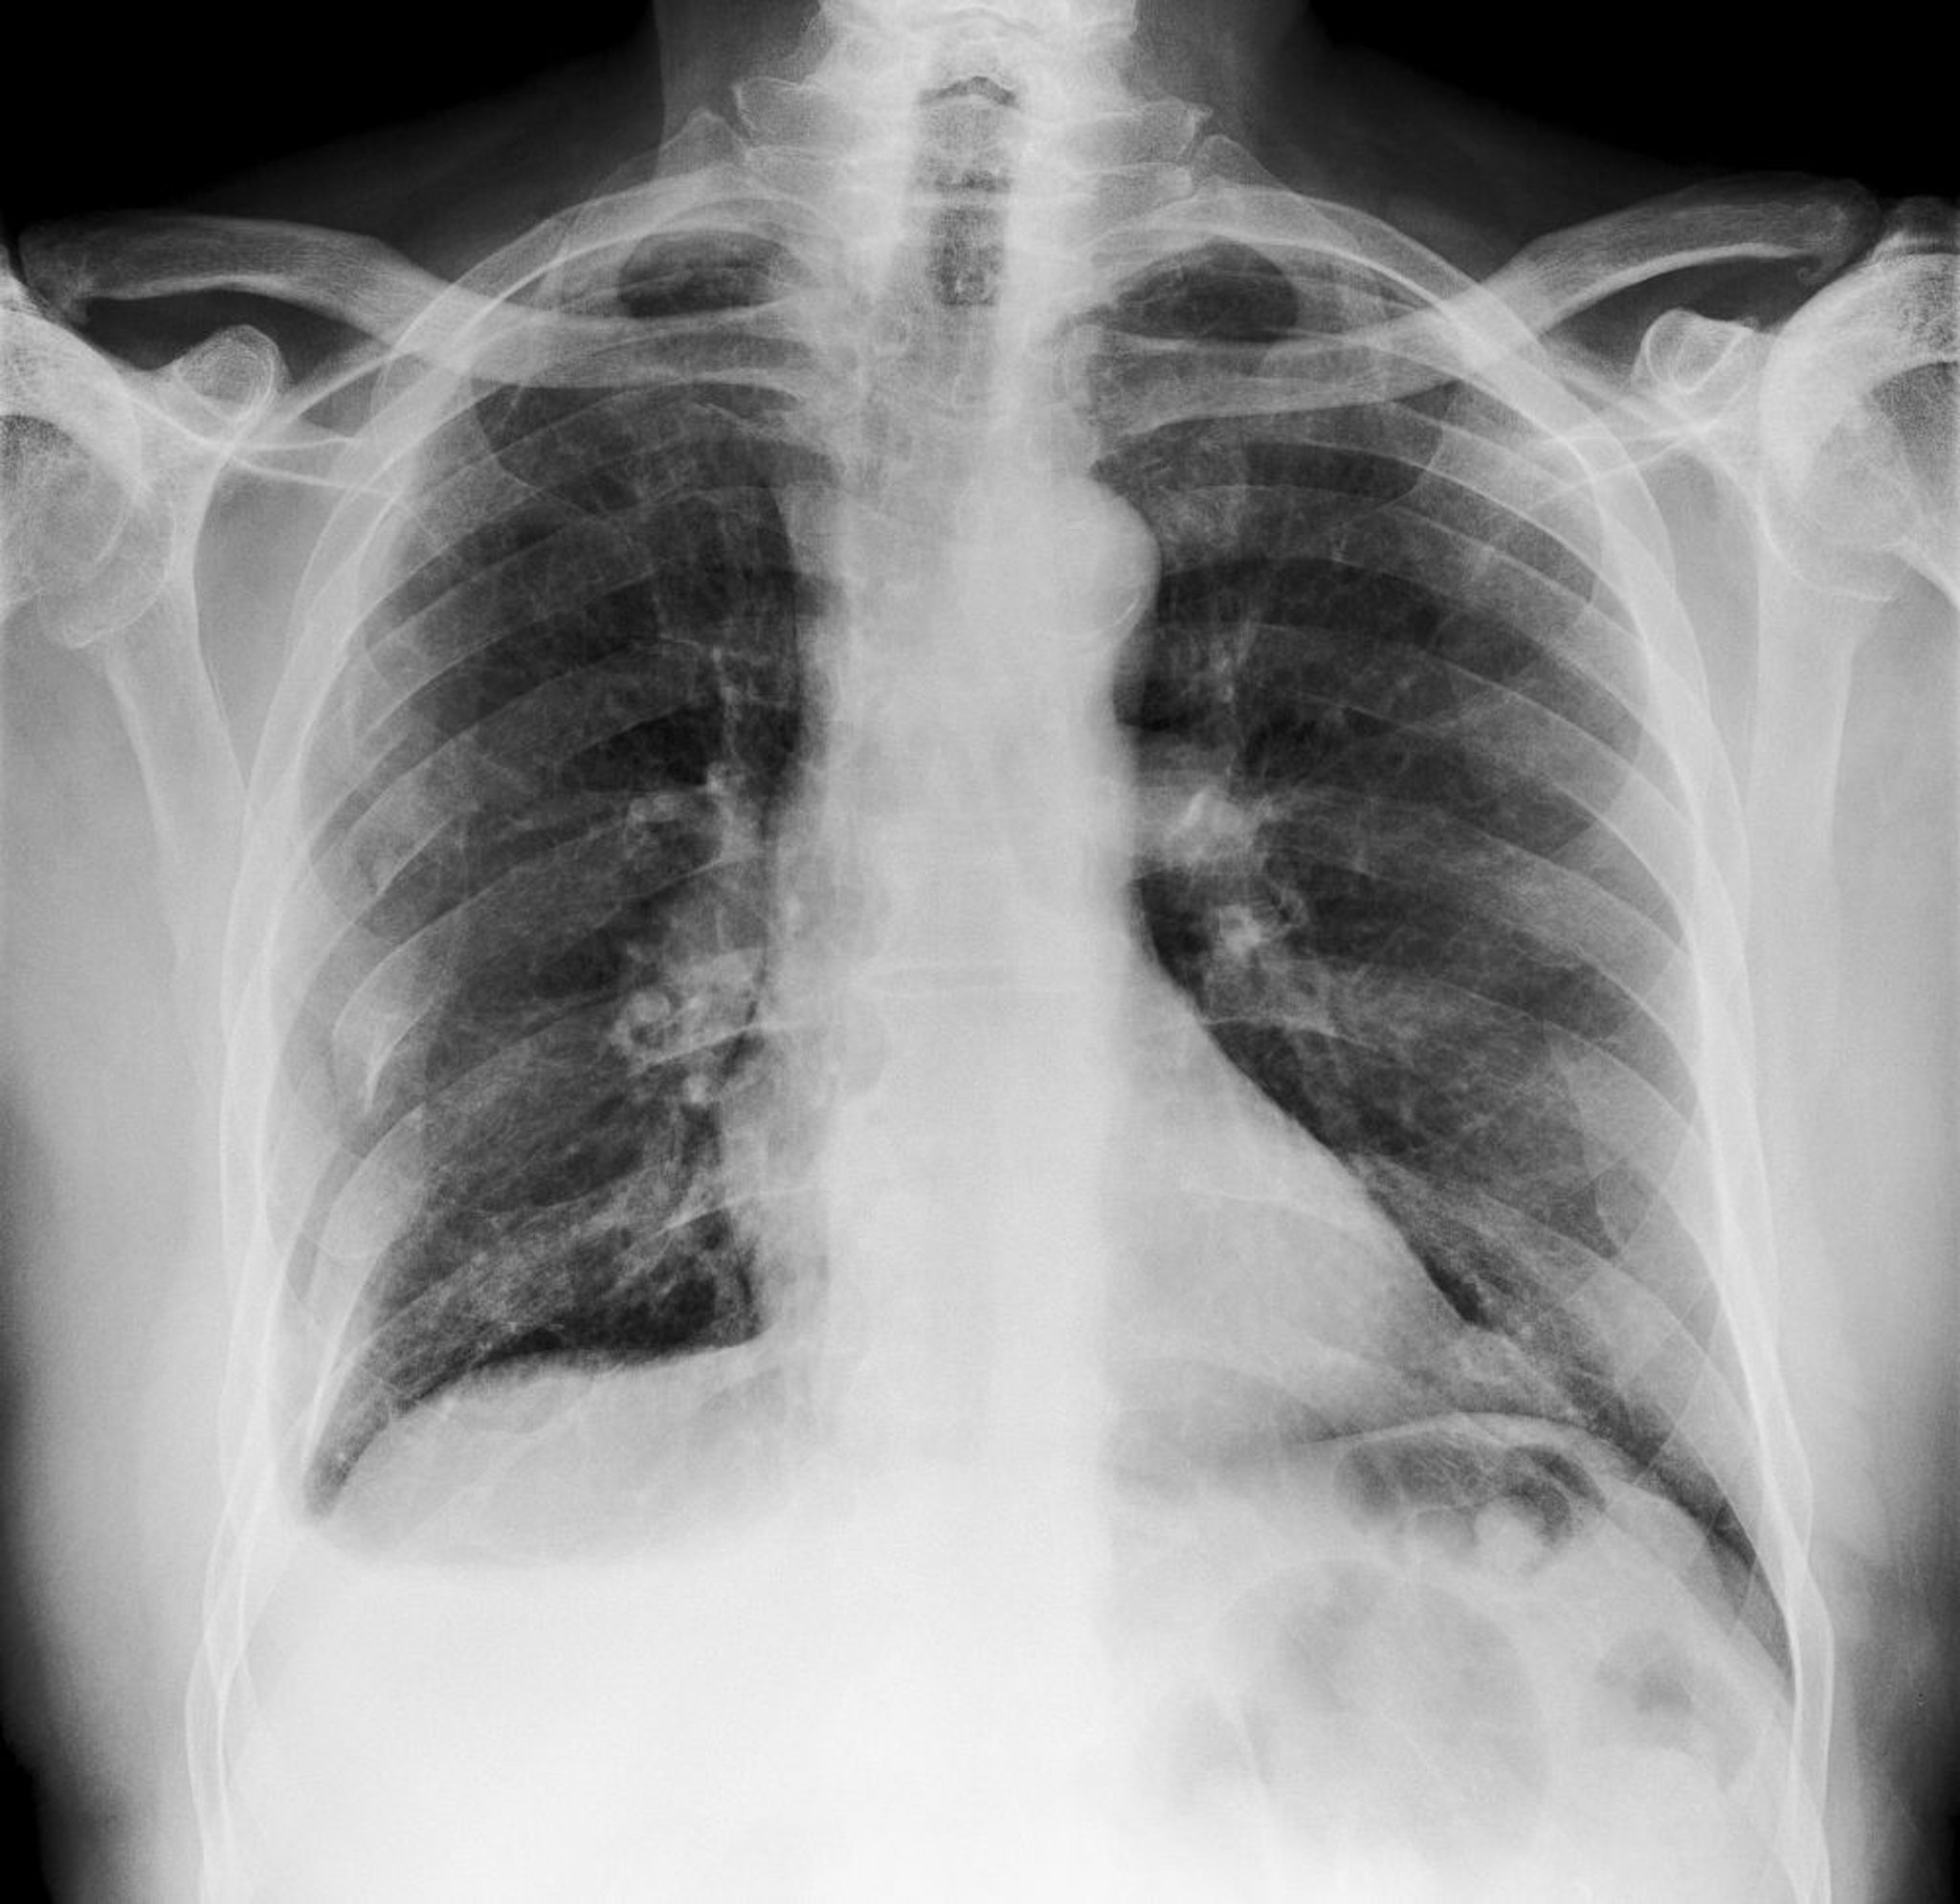

Essa radiografia do tórax mostra múltiplas fraturas nos arcos costais direitos (vistas à esquerda).